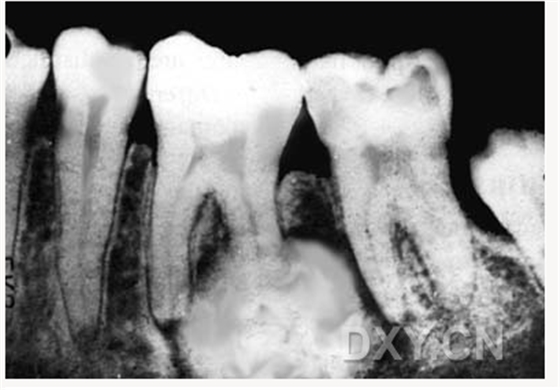

良性成牙骨質細胞瘤